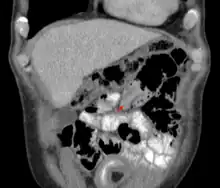

An intussusception as seen on CT | |

The cause in children is typically unknown; in adults a lead point is sometimes present.[1] Risk factors in children include certain infections, diseases like cystic fibrosis, and intestinal polyps.[1] Risk factors in adults include endometriosis, bowel adhesions, and intestinal tumors.[1] Diagnosis is often supported by medical imaging.[1] In children, ultrasound is preferred while in adults a CT scan is preferred.[1]

An intussusception is often suspected based on history and physical exam, including observation of Dance's sign. A digital rectal examination is particularly helpful in children, as part of the intussusceptum may be felt by the finger. A definite diagnosis often requires confirmation by diagnostic imaging modalities. Ultrasound is the imaging modality of choice for diagnosis and exclusion of intussusception, due to its high accuracy and lack of radiation. The appearance of target sign (also called "doughnut sign" on a sonograph, usually around 3 cm in diameter, confirms the diagnosis. The image seen on transverse sonography or computed tomography is that of a doughnut shape, created by the hyperechoic central core of bowel and mesentery surrounded by the hypoechoic outer edematous bowel.[11] In longitudinal imaging, intussusception resembles a sandwich.[11] It is also called "pseudokidney" sign because hyperechoic tubular centre is covered by a hypoechoic rim producing a kidney-like appearance.[12]